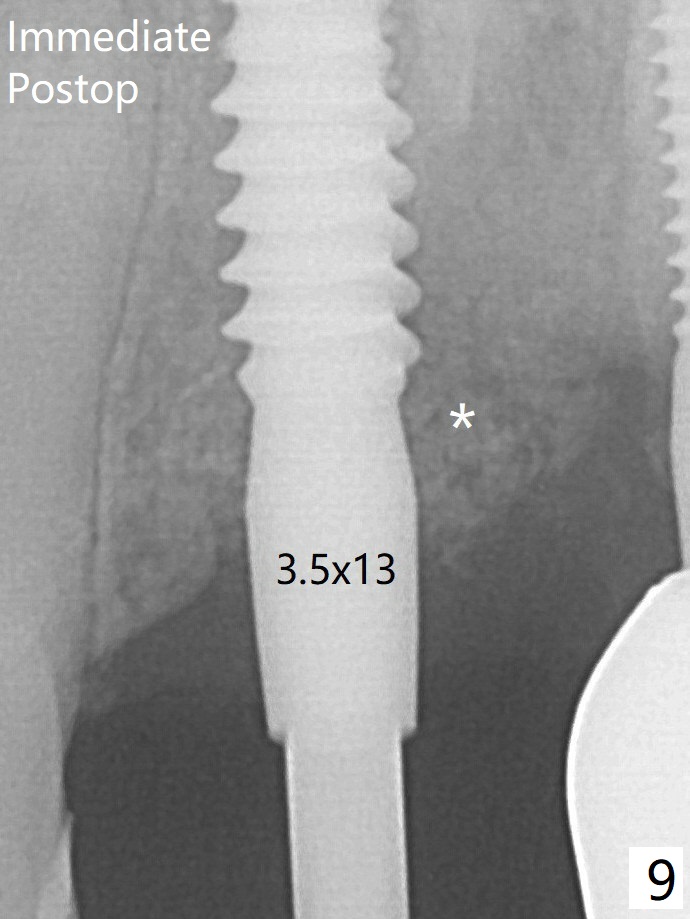

Allograft placed around the implant (Fig.9 *) appears to be able to prevent implant thread exposure 4 months postop (Fig.12).